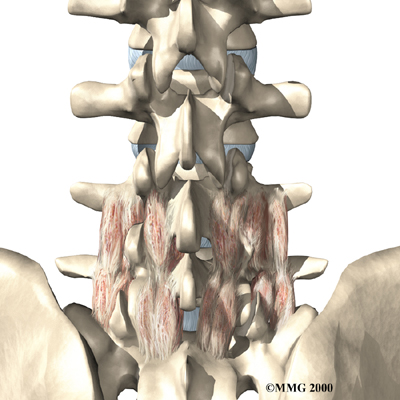

The human spine is formed by 24 spinal bones, called vertebrae. Vertebrae are stacked on top of one another to form the spinal column. The spinal column gives the body its form. It is the body's main upright support. The section of the spine in the lower back is known as the lumbar spine.

The lumbar spine is made up of the lower five vertebrae. Doctors often refer to these vertebrae as L1 to L5. These five vertebrae line up to give the low back a slight inward curve. The lowest vertebra of the lumbar spine, L5, connects to the top of the sacrum, a triangular bone at the base of the spine that fits between the two pelvic bones. Some people have an extra, or sixth, lumbar vertebra. This condition doesn't usually cause any particular problems.

Intervertebral discs separate the vertebrae. The discs are made of connective tissue. Connective tissue is the material that holds the living cells of the body together. Most connective tissue is made of fibers of a material called collagen. These fibers help the disc withstand tension and pressure.